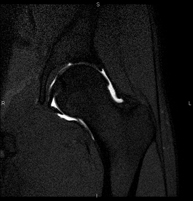

Exploració per estudiar lesions a l'articulació, com trencaments dels meniscals i dels lligaments creuats (únicament es poden detectar amb aquesta prova), condropatia o desgast del cartílag i moltes altres alteracions derivades de l'activitat esportiva i dels canvis degeneratius (osteoartrosi). La durada aproximada és de 18 minuts. No utilitza radiació ionitzant. - RM de Cama